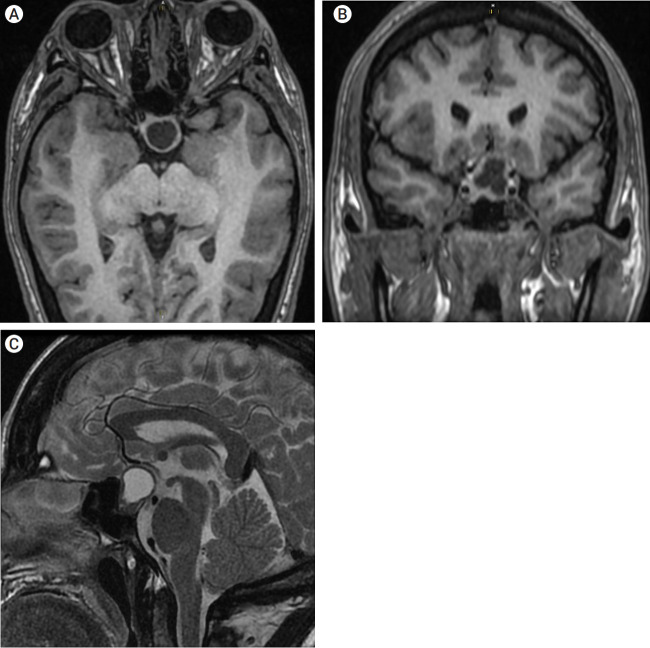

垂体手术后脑缺血并发症的报道并不多见。多种机制被提出,包括术后蛛网膜下腔出血引起的血管痉挛和延迟性脑缺血。鉴于这些情况下血管痉挛的病因不明,对其预防知之甚少。通过一份病例报告和文献回顾,作者警告术后识别可能表明脑血管痉挛风险增加的关键体征的重要性,必须及时识别,一旦出现这些症状就采取适当的治疗策略。

Cerebral ischemic complications after pituitary surgery are not frequently reported. Multiple mechanisms have been proposed, including vasospasm, and delayed cerebral ischemia resulting from postoperative subarachnoid bleeding. Given the unknown etiology of vasospasm following these situations, little is known about its prevention. Through a case report and bibliographic review, the authors warn about the importance of recognizing key signs postoperatively that could indicate increased risk for cerebral vasospasm and must be recognized in a timely manner, with appropriate treatment strategies implemented once these symptoms present.